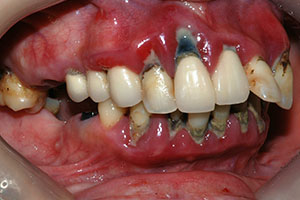

치료증례 전후사진

Before & After